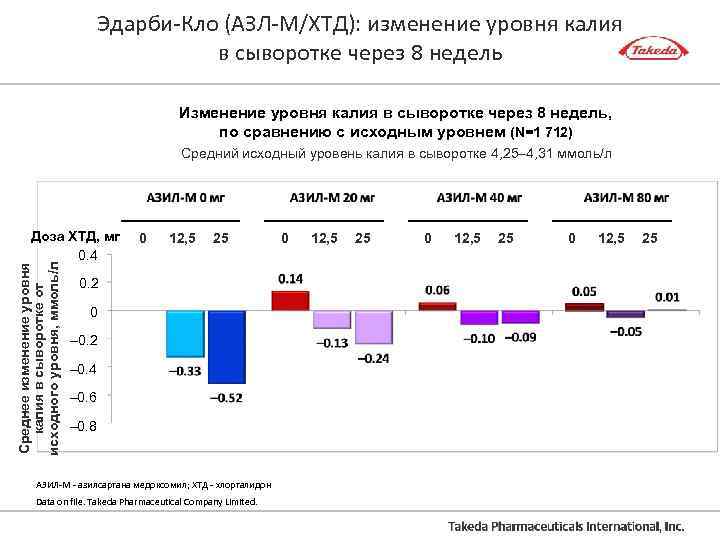

Эдарби-Кло (АЗЛ-М/ХТД): изменение уровня калия в сыворотке через 8 недель Изменение уровня калия в сыворотке через 8 недель, по сравнению с исходным уровнем (N=1 712) Средний исходный уровень калия в сыворотке 4, 25– 4, 31 ммоль/л Среднее изменение уровня калия в сыворотке от исходного уровня, ммоль/л Доза ХТД, мг 0. 4 0 12, 5 25 0. 2 0 – 0. 2 – 0. 4 – 0. 6 – 0. 8 АЗИЛ-М - азилсартана медоксомил; ХТД - хлорталидон Data on file. Takeda Pharmaceutical Company Limited. 0 12, 5 25

Эдарби-Кло (АЗЛ-М/ХТД): изменение уровня калия в сыворотке через 8 недель Изменение уровня калия в сыворотке через 8 недель, по сравнению с исходным уровнем (N=1 712) Средний исходный уровень калия в сыворотке 4, 25– 4, 31 ммоль/л Среднее изменение уровня калия в сыворотке от исходного уровня, ммоль/л Доза ХТД, мг 0. 4 0 12, 5 25 0. 2 0 – 0. 2 – 0. 4 – 0. 6 – 0. 8 АЗИЛ-М - азилсартана медоксомил; ХТД - хлорталидон Data on file. Takeda Pharmaceutical Company Limited. 0 12, 5 25